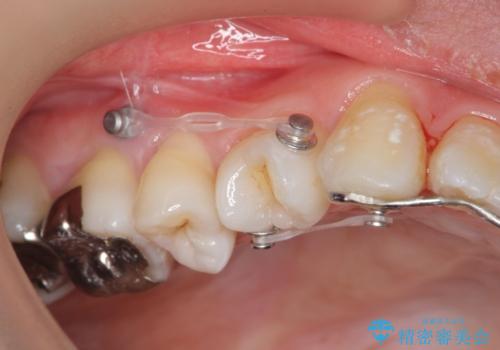

- 矯正装置

- インビザライン +部分ワイヤー矯正

マウスピースでは改善の難しい小臼歯のねじれをまず部分ワイヤー矯正で改善し、その後マウスピース矯正で前歯の突出感を改善します。

時間はかかりましたが、捻れ、かみ合わせ、前歯の角度の改善が達成され満足いただくことができました。